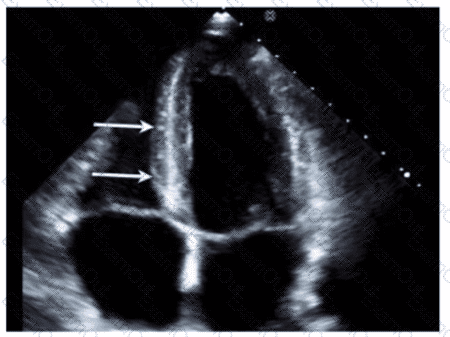

Which vessel is indicated by the arrow on this video?